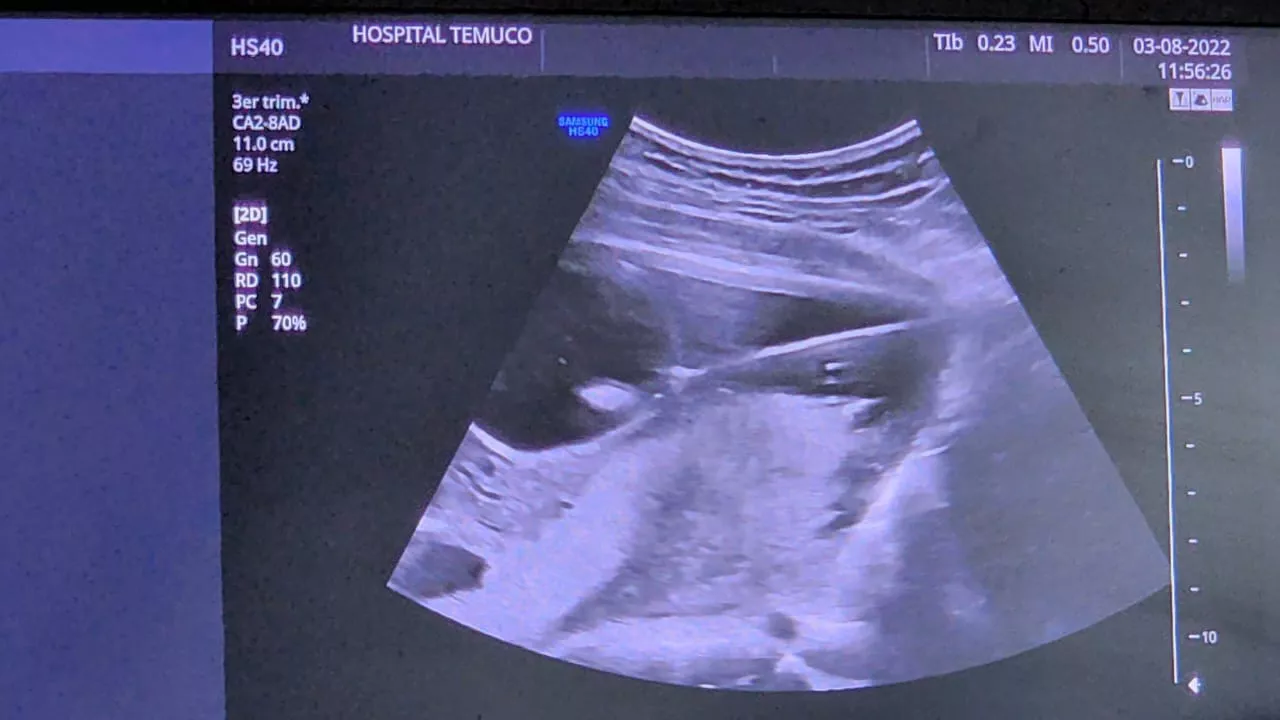

Un importante hito desarrolló el equipo de Alto Riesgo Obstétrico del Hospital Hernán Henríquez Aravena, al intervenir, dentro del útero de su madre, a un bebé de 19 semanas de gestación, con obstrucción en la vejiga, que hacía poco viable llevar a término el embarazo.

Según detalló el jefe del Servicio de Medicina Materno Fetal, Dr. Sebastián Martínez González, a cargo de realizar esta intervención, la obstrucción urinaria presentada por el bebé, básicamente no le permitía hacer pipí dentro del útero, lo que significó que en su vejiga se fuera acumulando la orina y eso, a la larga, traería problemas a los riñones los que al nacimiento no serían funcionales, pudiendo causar graves daños renales e incluso la muerte antes de nacer o posterior a su nacimiento.

La intervención realizada consistió en poner un drenaje en la vejiga, para que el pipí que el bebé no podía evacuar de manera natural, saliera hacia afuera; algo muy similar a lo que se hace en adultos con obstrucciones que se les pone un drenaje desde la vejiga hacia afuera, con la diferencia que esta vez, se hizo hacia el útero de la mamá, lo que permite que el feto pueda hacer pipí y seguir desarrollándose.